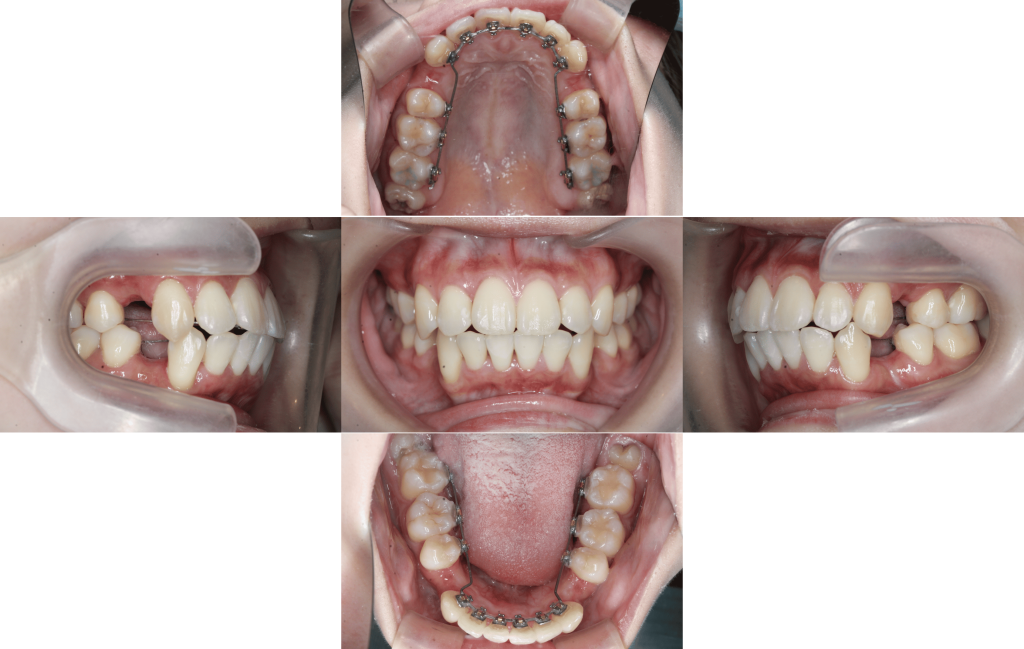

Before

初診

上下装置装着

約6か月経過

約1年経過

約1年6か月後

約1年10か月後

年齢層

20代

性別

女性

主訴

・前歯が出ている・横顔のシルエットを綺麗にしたい

治療費用

¥1.375.000

治療期間

1年10か月(治療中)

抜歯

上下顎左右第一小臼歯

矯正の装置

裏側矯正(マルチブラケット)

副作用、リスク

歯肉退縮,歯根吸収,疼痛,咬合の違和感,装置の違和感,虫歯,歯肉